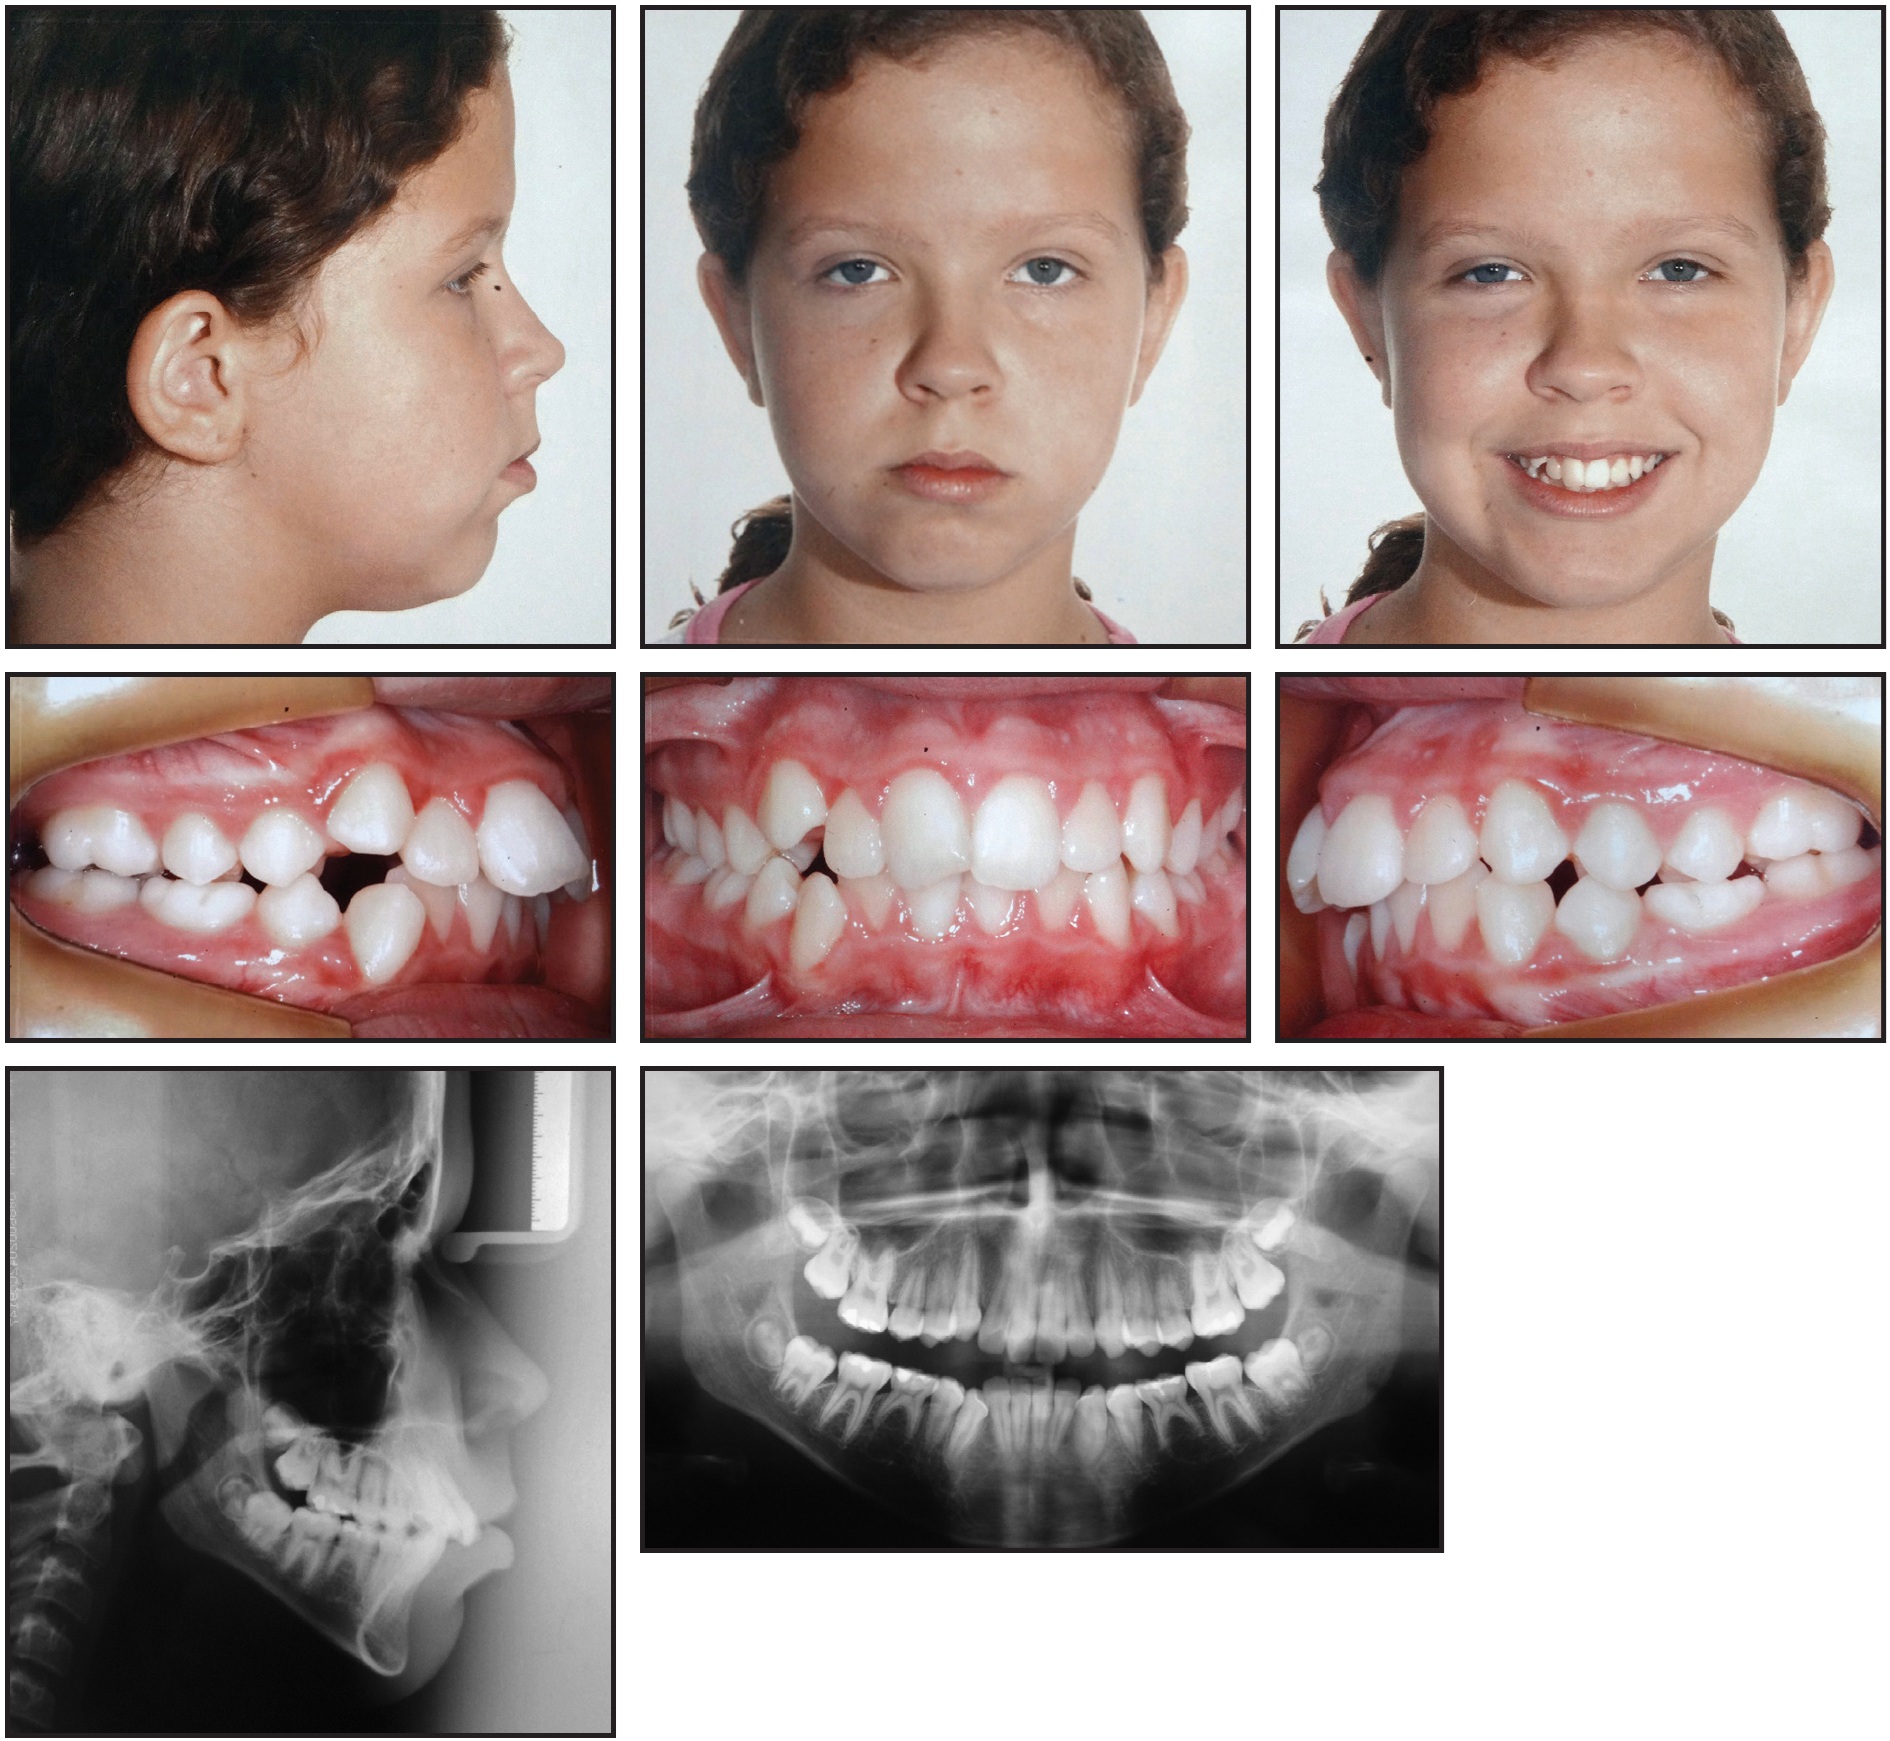

A 5-year-old female was referred by her dentist with the request to “correct the open bite.” The patient was in the mixed dentition and had a pacifier-sucking habit.

Clinical examination found a long lower face, convex facial profile, lack of lip closure, and normal nasolabial angle (Fig. 1).

Fig. 1 5-year-old female patient with pacifier-sucking habit, anterior open bite, and posterior crossbite before treatment.

Good oral hygiene and healthy gingival tissues were observed. The patient tended toward a Class II, division 1 malocclusion, with a distal-step molar relationship on the right and left sides; crossbite of the upper right deciduous canine, first molar, and second molar due to maxillary atresia; a 4.5mm anterior open bite; and a 7mm overjet. A metal crown was present on the upper left second deciduous molar. The upper midline was shifted 1mm to the left, but the lower midline coincided with the facial midline.

The patient exhibited mixed breathing, atypical swallowing and speech, and enlarged adenoids and tonsils; an otolaryngologist and a speech therapist had already been consulted. The panoramic radiograph showed congenital absence of the lower second premolars and third molars, with no evidence of calcification. Cephalometric analysis indicated a Class II skeletal pattern with maxillary prognathism and clockwise rotation of the mandible in relation to the skeletal base, a dolichofacial pattern, and a vertical growth trend (Table 1).